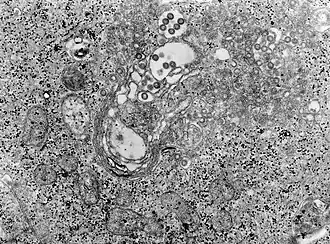

Les virions bunyavirus sont des particules enveloppées, à peu près sphériques, d'un diamètre de 70 à 120 nanomètres[6].

La nucléocapside est constituée par la nucléoprotéine N associée aux ARN monocaténaires, formant des ribonucléoprotéines (RNP). Les RNP apparaissent sous forme circulaire dont les extrémités 3' et 5' ont des séquences complémentaires inversées[6],[7].

Multiplication

Les virus RVF infectent la cellule-hôte par endocytose via des récepteurs, suivie d'une fusion de membranes, pour libérer des nucléocapsides dans le cytoplasme cellulaire. Toutes les étapes du cycle viral, dont la réplication, ont lieu dans le cytoplasme et, selon le type de cellule, au niveau de l'appareil de Golgi[6],[7].